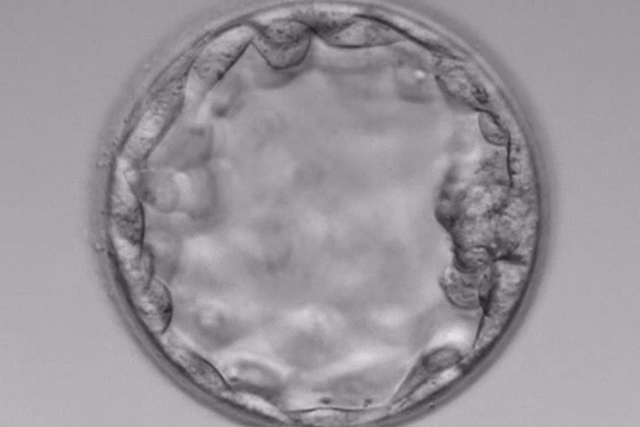

経験豊富な培養士在籍

培養士外来あり

体外受精や受精卵の事etc

素朴な疑問を気軽に相談